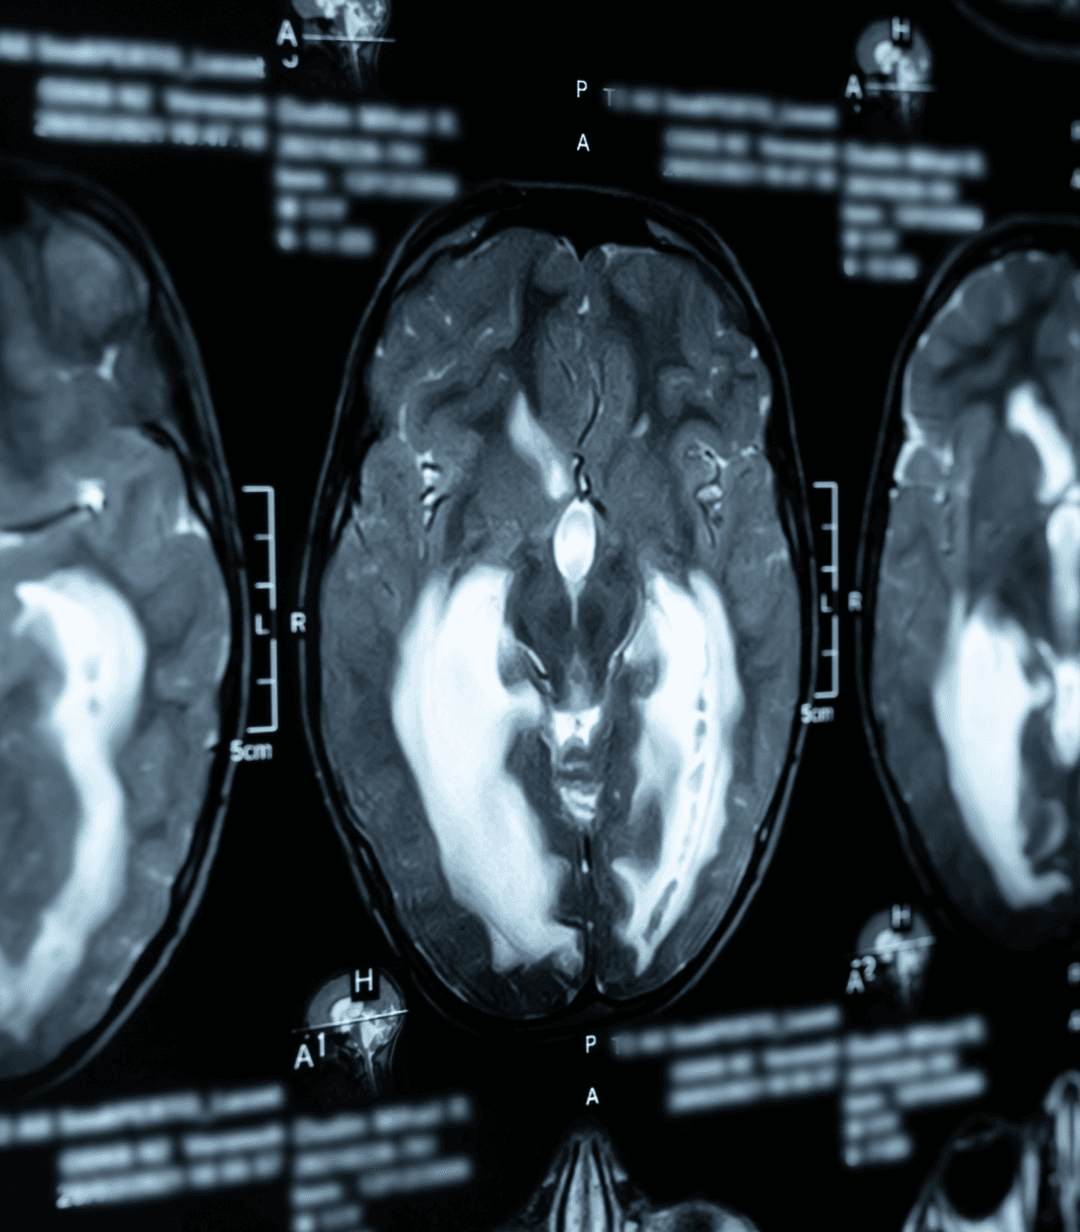

High-field strength MRI utilizes powerful magnetic fields and advanced computing to produce exceptionally detailed images, allowing for more accurate diagnoses in less time

High-Field Strength MRI

Superior image resolution for detecting the finest anatomical details

Neurological & ENT